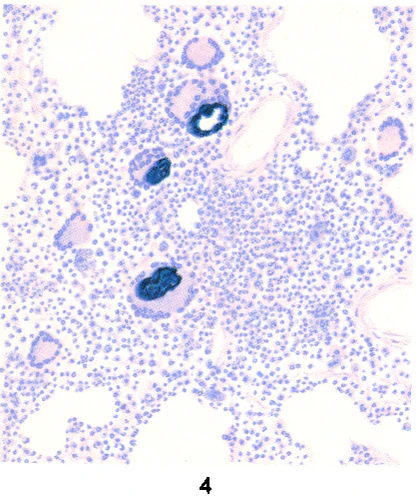

При бериллиозе морфологические изменения характеризуются диффузным поражением обоих лёгких и плевры, распространённым гранулёматозом и хроническим межуточным (синоним «промежуточный») пролиферативным процессом, локализующимся в перегородках альвеол, под плеврой, перибронхиально, периваскулярно. Гранулёмы — серовато-белого цвета, плотной консистенции, размером от 0,2 до 1,5 см. Гранулёма состоит в основном из гистиоцитов, эпителиоидных клеток с примесью (главным образом по периферии) лимфоидных, плазматических и гигантских клеток типа клеток инородных тел (цветн. рис. 4—9). Гигантские клетки содержат кристаллические образования. В дальнейшем происходит созревание клеток гранулёмы с появлением в ней фибробластов. Фибробласты начинают продуцировать коллагеновые волокна, и процесс завершается развитием на месте гранулёмы соединительнотканного узелка, который нередко подвергается гиалинозу. В гранулёмах обнаруживают типичные для Б. конхоидальные (раковинообразные) тельца диаметром от 2,5 до 10 мкм, которые могут образовывать скопления диаметром до 190 мкм. Иногда они располагаются в многоядерных гигантских клетках. Конхоидальные тельца окрашиваются гематоксилином в синий, сине-фиолетовый цвет, иногда дают положительную реакцию на железо, имеют вид флюоресцирующих голубоватых зёрен при освещении ультрафиолетовыми лучами. Наряду с гранулёматозом в межальвеолярных перегородках наблюдается диффузный пролиферативный процесс с наличием гистиоцитов, лимфоидных, плазматических клеток, фибробластов, заканчивающийся диффузным пневмосклерозом. Наблюдается бронхит, возможно развитие бронхоэктазов. Встречаются участки ателектаза и эмфиземы. В кровеносных сосудах могут иметь место эндартериит, эндофлебит, тромбозы. Описанные изменения в лёгких обычно приводят к развитию лёгочного сердца[6].